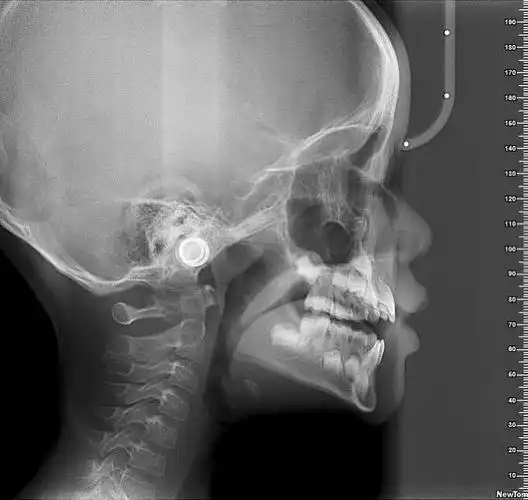

【头颅侧位片】那么牙片的辐射危害大吗?

可拍全景片,头颅侧位片,牙颌面锥形束ct ,全方位

这可是从国外引进的可以拍曲面断层片和头颅侧位片的ct一体机,要知道